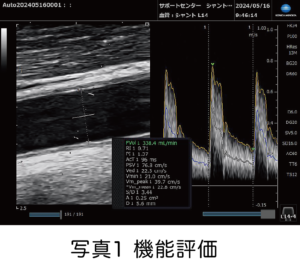

そのような場合、超音波診断装置を使用してシャントに流れている血流量(シャント血流量Flow Volume:FV)や血液の流れにくさ(血管抵抗指数Resistance Index:RI)など、血液透析を行うに十分な能力を持っているかを評価する「機能評価(写真1)」と血管全体の把握や機能低下の原因となっている病変部の詮索(狭窄の程度)などを評価する「形態評価(写真2)」を行っております。